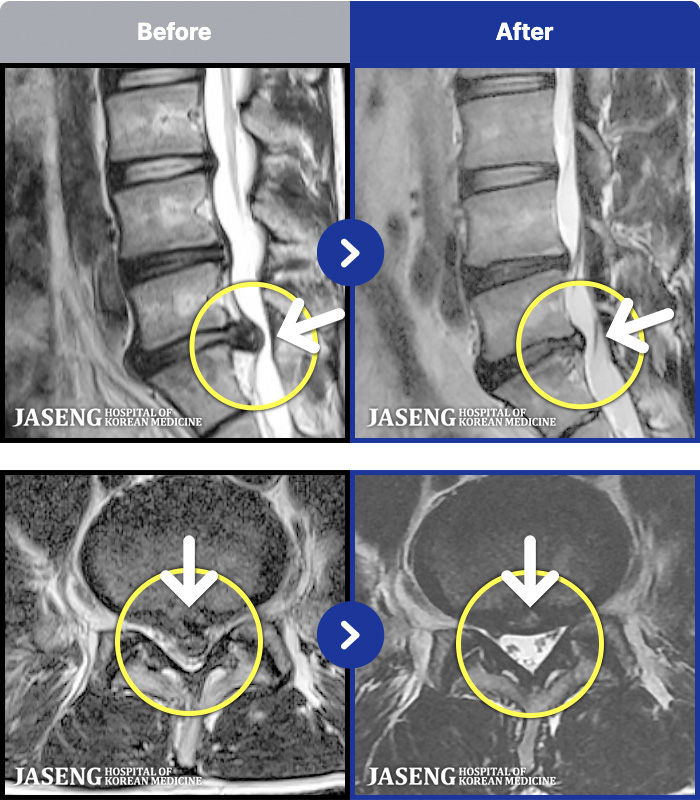

1,287 MRI ũ ʸ Ȯϼ.